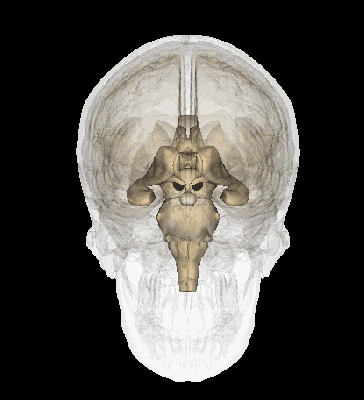

腦干主要是由中腦、腦橋、延髓三部分組成,被醫(yī)生稱為“生命禁區(qū)”,有著密集排列著顱神經(jīng)的核團(tuán),及肢體與大腦聯(lián)系的上下傳導(dǎo)束,另外腦干中還有維持我們清醒的腦干上行激活系統(tǒng)和心血管和呼吸的控制中樞。

主要是負(fù)責(zé)調(diào)節(jié)比較復(fù)雜的反射活動(dòng),包括心跳、呼吸、消化、體溫、覺醒等重要的生理機(jī)能,從而維持人類個(gè)體生命。

腦干的功能總結(jié)如下:

心血管中樞和呼吸中樞;

維持我們覺醒的腦干上行激活系統(tǒng);

大腦與脊髓聯(lián)絡(luò)的必經(jīng)之路,包括四肢的感覺與運(yùn)動(dòng)等;

腦干有多個(gè)顱神經(jīng)核團(tuán),用以維持顱面部神經(jīng)活動(dòng)。